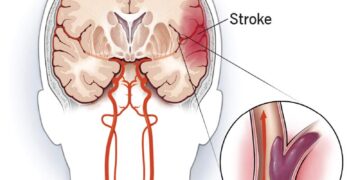

Međutim, pojedinci koji su primili stimulaciju živca vagusa imali su jače reakcije mozga na negativne/uznemirujuće slike, a smanjene odgovore na ugodne slike kada se mjeri fMRI. Suprotno je vrijedilo za kontrolnu skupinu.

“Rezultati studije predstavljaju prvi korak prema razumijevanju kako se neinvazivna stimulacija živca vagusa može učinkovito koristiti kao alat za liječenje pacijenata s PTSP-om, generaliziranom anksioznošću i drugim poremećajima koji uključuju pojačan odgovor na percipirane prijetnje”, rekao je Lerman.